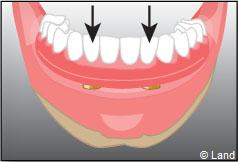

Deux techniques sont possibles. Elles font appel à la barre de rétention ou aux boutons-pressions.

Situation clinique initiale